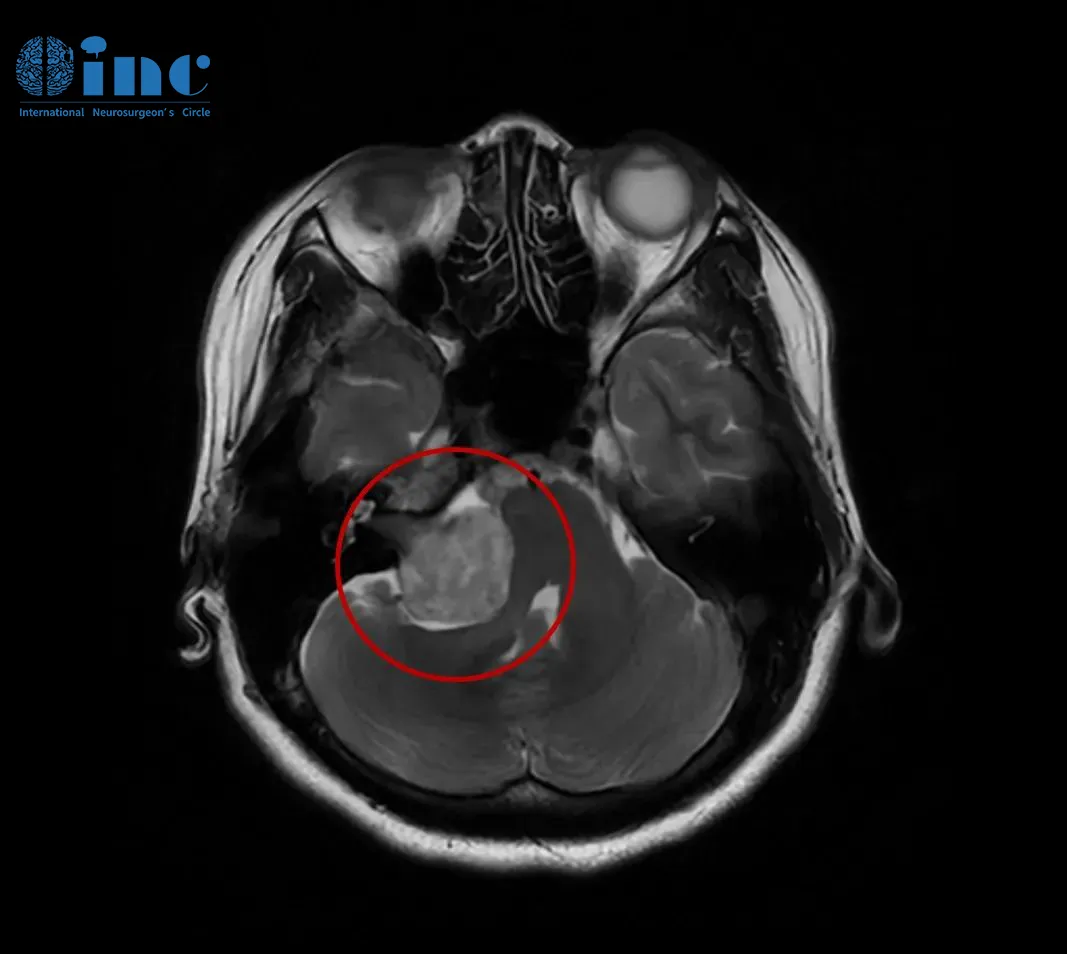

此次,她接受了头颅核磁共振(MRI)检查,结果最终明确了病因——右侧桥小脑角区前庭神经鞘瘤。肿瘤最大直径约35毫米(包括内听道内的部分),已经压迫到脑干,导致桥脑及右侧桥臂受压,第四脑室形态发生改变。

听神经瘤诊断的金标准为颅脑磁共振成像(MRI)增强扫描。该检查能够清晰显示内听道或桥小脑角区的肿瘤位置、大小及其与周围神经血管的解剖关系,对微小肿瘤的检出率较高,诊断准确率超过95%;CT检查虽可辅助评估骨质结构情况,但其软组织分辨率相对较低,通常作为补充检查手段。